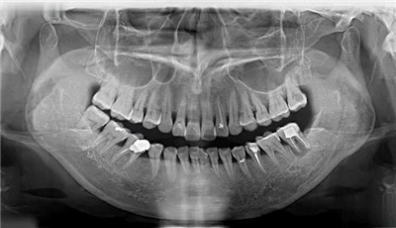

阅读全文生活中有很多人 因为牙齿缺失 咀嚼受到严重影响 生活质量大打折扣 许多人认为缺一两颗牙不要紧,实在不行就做个活动假牙凑合着,而将做种植牙视为没有必要之举。 其实,这是错误的想法。长期缺牙会引发系列问题:吃东西咬不碎,营养吸收不了,普遍会...